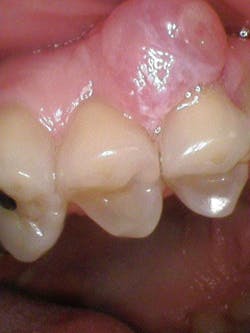

In this particular case, the patient was referred to an oral surgeon for an assessment and biopsy. The lesion was removed and sent to pathology with a definitive diagnosis of peripheral ossifying fibroma (figures 4–6). The gingival defect created by the removal of the fibroma was allowed to heal by secondary intention and will likely undergo a free gingival graft later to reconstruct the attached gingival margin. The patient managed well without complications.